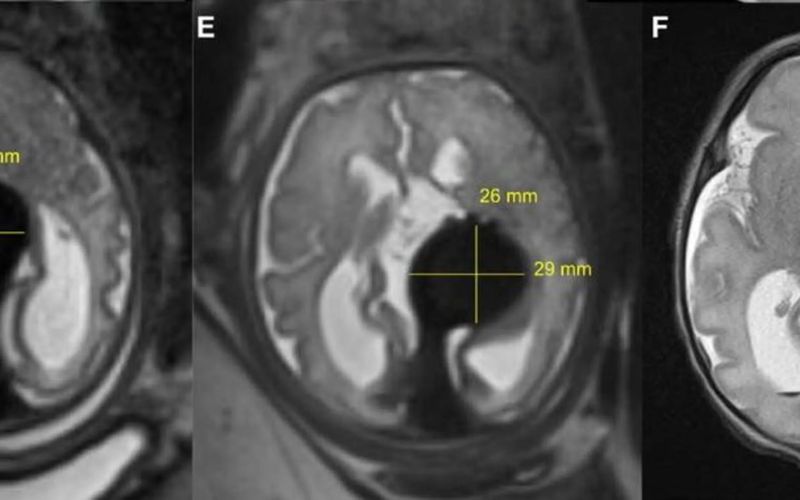

Luego de hacer varios estudios, los resultados no fueron los mejores, arrojaron que la menor tenía la malformación de la vena Galeno (VOGM) algo muy preocupante, después de recibir esta triste noticia los médicos me comentaron sobre una cirugía que se podría llegar a practicar a mi pequeña bebe dentro de mi vientre y los posibles riesgos que pudiera tener.

Tres semanas después de su nacimiento mediante una resonancia magnética, los médicos pudieron ver que la pequeña no necesitaba asistencia cardiovascular, pues no mostró flujos sanguíneos anormales.